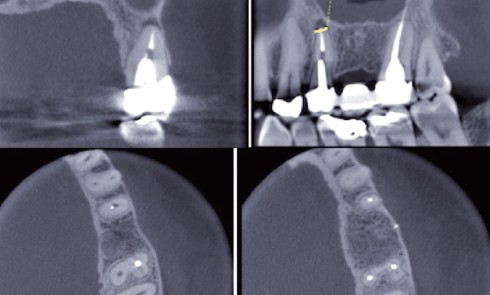

Article réservé à nos abonnés S’abstenir ou (ré)intervenir ? Quels critères décisionnels ? Apport de l’imagerie 3D

L’objectif du traitement endodontique est de prévenir l’apparition d’une parodontite apicale ou de la traiter si la lésion est déjà...